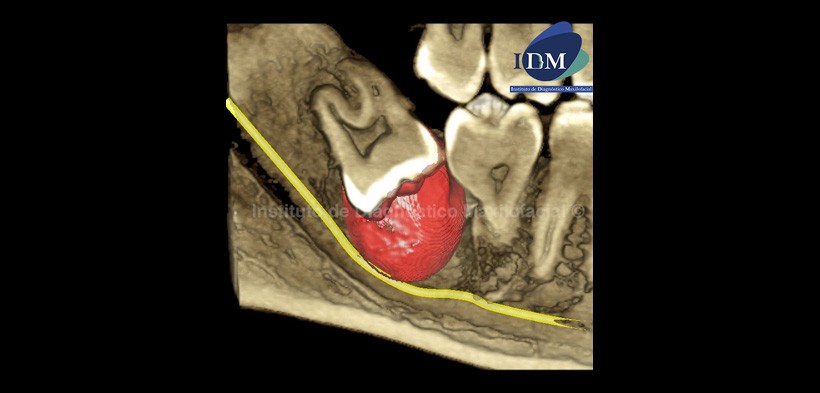

Al estudio con tomografía volumétrica, en el corte tangencial (Fig. 2) confirmamos la formación quística envolviendo la corona de la pieza 4.8, condicionando la posición invertida de esta, con las raíces próximas al borde anterior de la rama ascendente. En el corte axial (Fig. 3) se observa el proceso osteolítico en contacto con la raíz distal de la pieza 4.7, así como el adelgazamiento de la tabla ósea lingual. En el corte transaxial (Fig. 4) se observa el origen de la lesión a nivel de la unión cemento-adamantina (UCA) de la pieza 4.8 y el desplazamiento basal del conducto dentario inferior.

En la reconstrucción tridimensional se observa de forma didáctica la extensión de la lesión y la relación con sus estructuras vecinas (Fig.5).